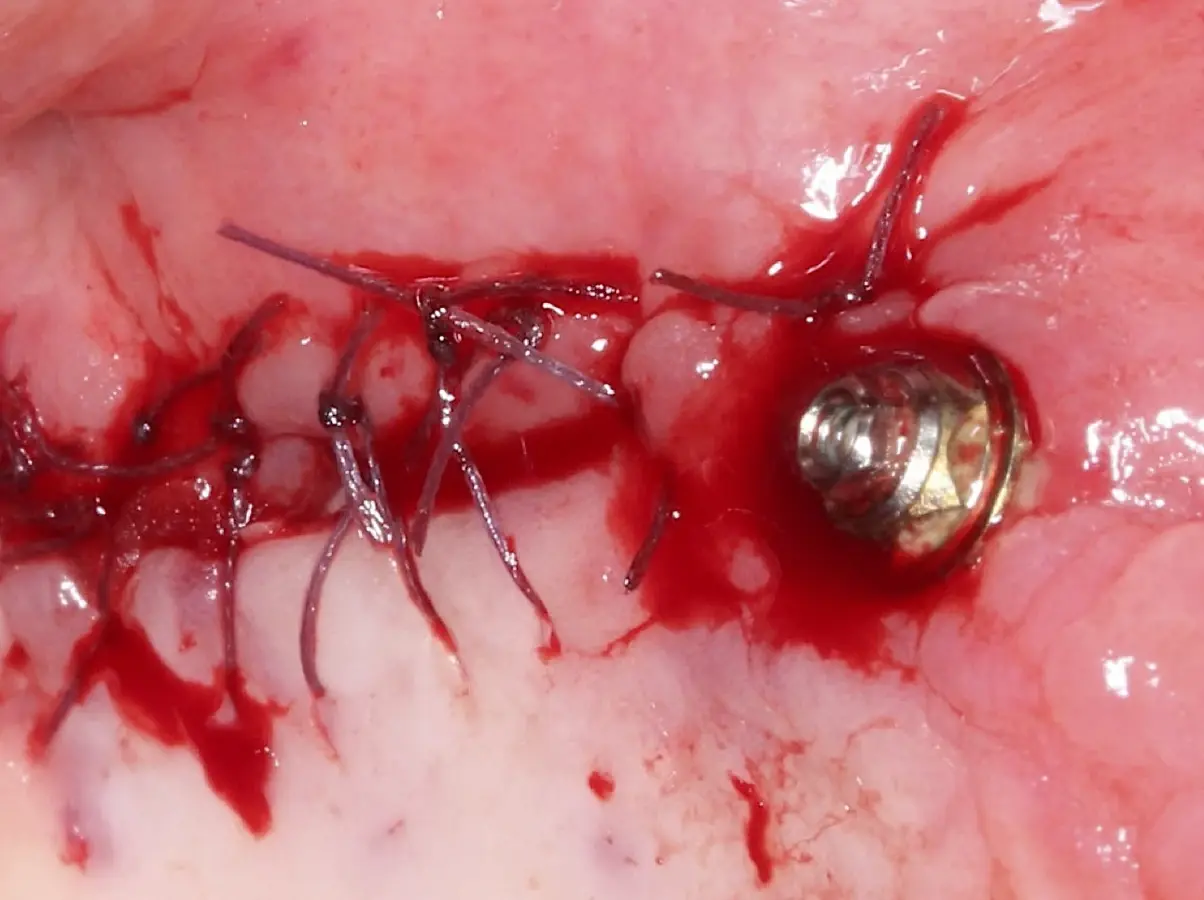

La técnica se inicia con la colocación de anestesia infiltrativa, posteriormente se realiza una incisión crestal o paracrestal con posibles liberantes verticales que deben de estar alejadas por lo menos 5 mm de los límites de la futura ventana y sobrepasar la línea mucogingival. Se realiza una elevación de colgajo, se inicia la antrostomía y antroplastía. Para ello, se emplea el inserto redondo diamantado de corte al momento de delimitar los bordes de la ventana de acceso. Luego se cambia al inserto aserrado liso de calibre fino con superficie diamantada, para profundizar y eliminar el hueso en el contorno de la ventana. Una vez que se traslucen los tejidos, se puede optar por el retiro de la tapa ósea o el levantamiento de ésta junto con la membrana.

El tipo de inserto a ser utilizado dependerá del espesor de la pared ósea. Si la pared es menor a 0.5 mm, es mejor utilizar insertos de desgaste para prevenir la ruptura de la membrana de Schneider; si el espesor es mayor a 0.5 mm, se puede utilizar insertos de corte de espesor medio (Figura 3).

El clínico puede retirar la tabla ósea o introducirla como “tienda de campaña” dentro del seno maxilar. En cualquiera de las alternativas, es importante evaluar la presencia de tabiques óseos y de la arteria postero alveolar superior.